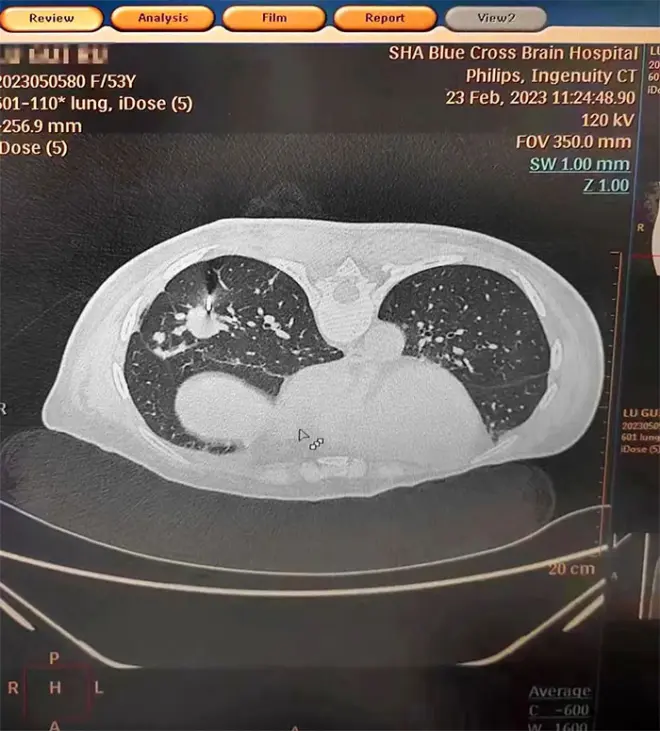

近日,张泽明主任成功开展一例CT引导下经皮肺穿刺活检术。53岁女性患者陆某(化名)有乳腺癌病史,近期反复咳嗽、咳痰就医,行肺部CT检查提示肺部多发占位。

▲ CT检查提示肺部多发占位

由于患者肺部病变位置靠近外周,气管镜下难以取得病变部位标本。经医院肿瘤科(放疗)、十楼重症监护病房、医学影像科开展多学科讨论,并经反复评估后,决定行CT引导下经皮肺穿刺活检,以明确诊断。